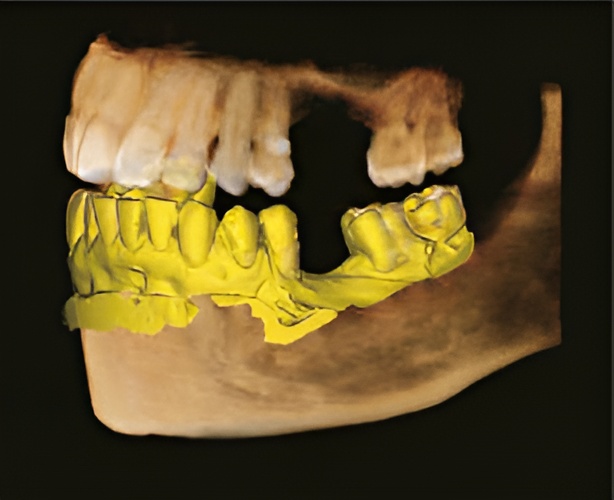

3D-сканирование модели

3D-сканирование модели позволяет пользователям хранить гипсовые слепки в цифровом виде для упрощения управления цифровыми процессами.

Цифровые модели

- Интеграция с CAD/CAM-системами.

- Достаточный уровень детализации для создания хирургического шаблона.